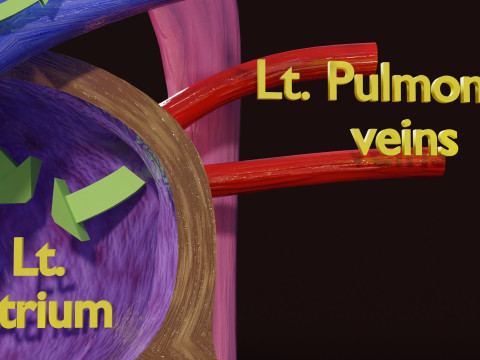

The model meshes include adult circulation versus circulation in Tetralogy of Fallot (TAF), arrow labels and text labels. The blood flow in a patient with Tetralogy of Fallot is outlined in this model. To contrast it to normal blood circulation a separate model of normal circulation is included. The Tetralogy of Fallot (OVER RIDING OF AORTA, PUL STENOSIS, VENTRICULAR SEPTAL DEFECT, RIGHT VENTRICULAR HYPERTROPHY), fossa, ligament teres , venosus, and arteriosus are duly depicted with proper labelling and blood flow directional arrows. Excellent model for teaching, demonstration and knowlegde of human body. The models include both procedural and image textures blend files separately. The texture file include diffuse, roughness and normal png and jpeg based on non overlapping UV maps.